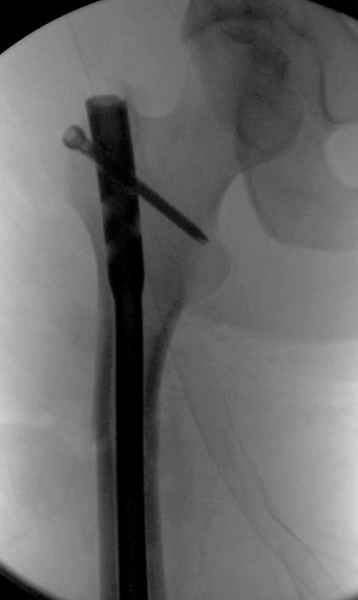

Второй случай тоже репозиция из малого доступа, больному 19 лет, множественные огнестрельные повреждениия конечностей, живота и черепа, правая конечность холодная, без пульсации. Ортопедический диагноз: огнестрельный перелом правого бедра. При срочной ангиографии повреждения сосудов не подтвердилось, конечность из-за ургентности состояния больного зафиксирована временным наружным фиксатором и больной оставлен на операционном столе для срочной лапаротомии хирургической службой.

Больной долго оставался нестабильным, только на 14 день удалось заменить на антеградный интромедуллярный штифт TFN (trochanteric femoral nail) SmithNephew. После неудачной попытки закрытой репозиции, несмотря на использование "joystick", проксимальный стержень от

наружного фиксатора, (перелом начал срастаться) репозицию провели из малого доступа, затем остальные этапы операции.

Случай был представлен из-за того, что больного оперировали после наружной фиксации и был риск инфекцирования через места проведения стержней (на снимках), прошло больше 3 месяцев, выписан из амбулаторной службы из-за отсутсвия надобности дальнейшего наблюдения.